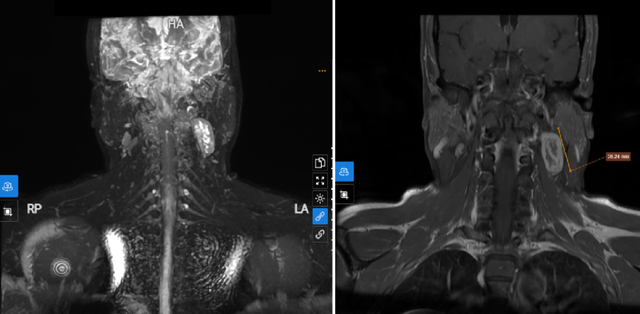

Tổn thương phát hiện trên phim chụp MRI vùng cổ. Ảnh: BVCC

Ngay lập tức, bệnh nhân được chỉ định thực hiện chụp MRI vùng cổ. Kết quả phát hiện hình ảnh thoát vị đĩa đệm cột sống cổ C4/5, C5/6, C6/7 thể trung tâm, không chèn ép tủy và rễ thần kinh.

Đáng chú ý, trên phim chụp phát hiện tổn thương dạng đặc phần mềm vùng góc hàm trái, hướng đến nguồn gốc thần kinh, nghi ngờ liên quan đến nhánh thần kinh C2-3 cổ trái. Bệnh nhân được sinh thiết dưới hướng dẫn của siêu âm đánh giá mô bệnh học, cho kết quả chẩn đoán xác định đó là theo dõi u tế bào Schwannoma.